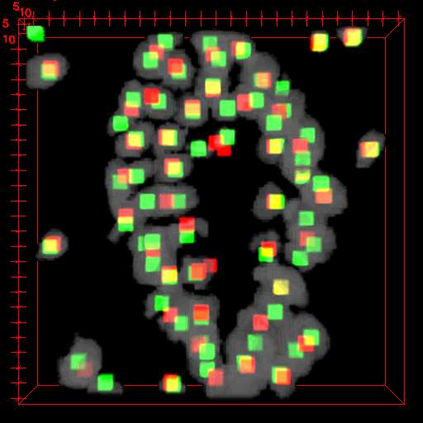

Robust and accurate nuclei centroid detection is important for the understanding of biological structures in fluorescence microscopy images. Existing automated nuclei localization methods face three main challenges: (1) Most of object detection methods work only on 2D images and are difficult to extend to 3D volumes; (2) Segmentation-based models can be used on 3D volumes but it is computational expensive for large microscopy volumes and they have difficulty distinguishing different instances of objects; (3) Hand annotated ground truth is limited for 3D microscopy volumes. To address these issues, we present a scalable approach for nuclei centroid detection of 3D microscopy volumes. We describe the RCNN-SliceNet to detect 2D nuclei centroids for each slice of the volume from different directions and 3D agglomerative hierarchical clustering (AHC) is used to estimate the 3D centroids of nuclei in a volume. The model was trained with the synthetic microscopy data generated using Spatially Constrained Cycle-Consistent Adversarial Networks (SpCycleGAN) and tested on different types of real 3D microscopy data. Extensive experimental results demonstrate that our proposed method can accurately count and detect the nuclei centroids in a 3D microscopy volume.